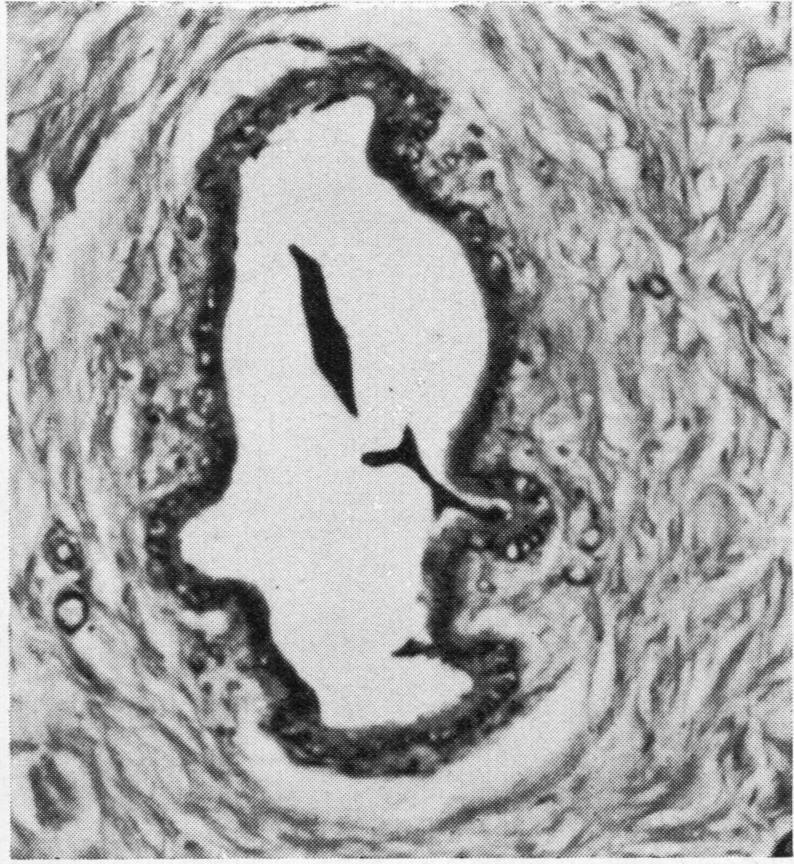

The histological appearances of the breast in a patient with mucoviscidosis are those of complete lobular agenesis. Ducts and ductules are well developed, and there is abundant fibrous tissue giving the breast a normal contour. The appearances are contrasted with those of gynaecomastia, and the aetiology is discussed.